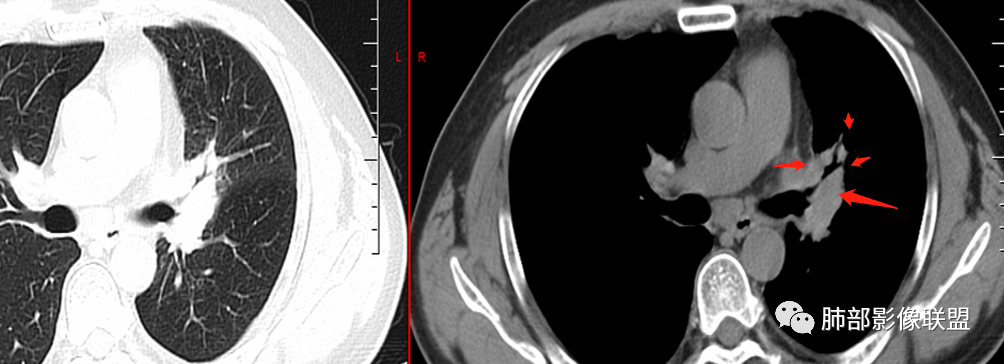

仔细看延迟期淋巴结内有坏死,结核还真要考虑了 医学百科网 | YxBaike.Com

这些淋巴结融合,中心低密度坏死,为结核的特点

我就想看支气管壁的破坏情况,但是不是很清楚,尖后段支气管远端似乎堵了,但好像又有穿出来,如果有穿出来就是狭窄后扩张,那肯定是结核的特点;肺门区前段和舌段的支气管就符合结核的特点:狭窄后扩张。

结果:

小鱼: 医学百科网 | YxBaike.Com

果然是结核 医学百科网 | YxBaike.Com

6.隆突下见增大淋巴结,环形强化为主。 医学百科网 | YxBaike.Com

2. 小细胞癌:异常肿大淋巴结可以形成肺门区多处支气管管腔狭窄。

支气管隆突下增大淋巴结通常不符合左肺上叶癌肿的迁徙途经。 医学百科网 | YxBaike.Com

3.慢性感染:累及较大支气管且形成块影,常见的有支气管侵袭性曲霉病等真菌感染及结核等。 医学百科网 | YxBaike.Com

结核病常见,正如有老师分析,应当纳入考虑范围。支气管多处狭窄,或断断续续,符合结核的特点。 医学百科网 | YxBaike.Com